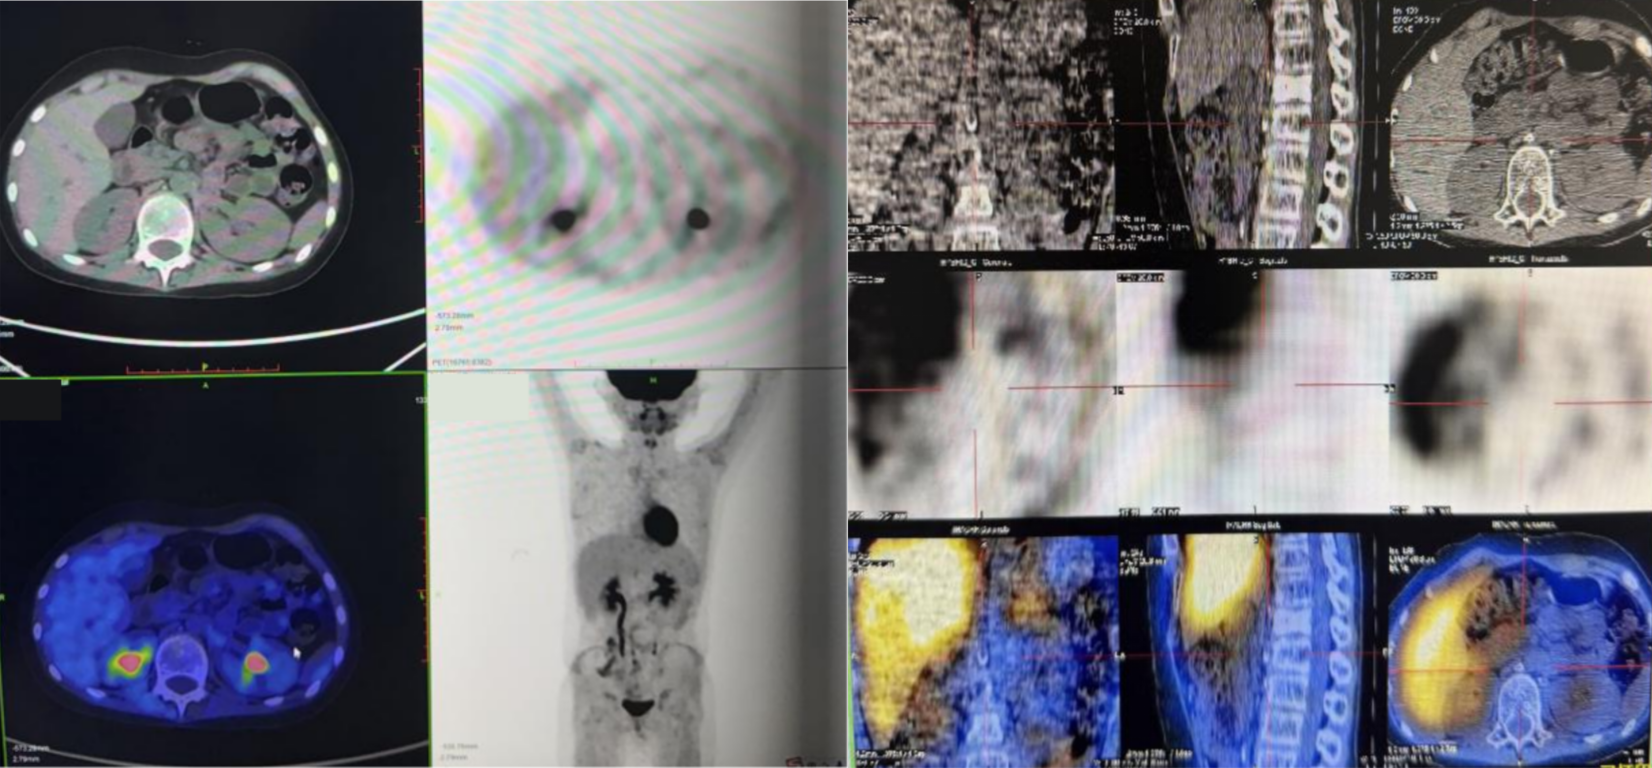

PET-CT(2022.5.19)

1. 左侧中下腹左肾旁不规则巨大肿物,PET显示异常放射性浓聚,考虑为恶性,神经母细胞瘤可能性大。

2. 左侧中下颈、锁区,后纵隔食管周围,坐下后胸膜下、双侧膈脚后、腹膜后腹主动脉及下腔静脉周围、双侧髂总血管周围、髂脉区多发结节及肿物,PET显示异常放射性浓聚,考虑为淋巴结转移。

3. 所见全身多发骨骼骨质密度不均及骨质破坏,PET显示异常放射性浓聚,考虑为转移。